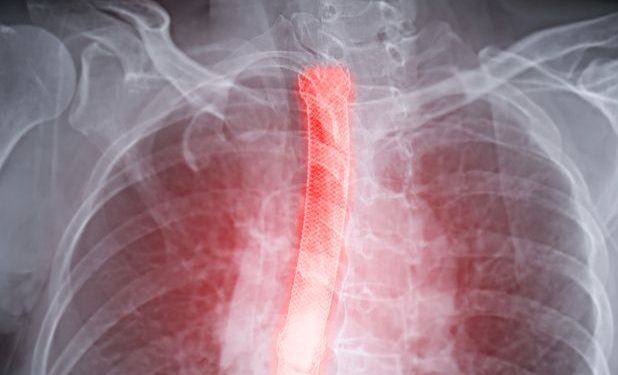

Symptoms of esophagitis can include a sore throat or a sensation that something is stuck in the throat. You may cough or spit up blood. You may have trouble swallowing, especially when bending or straining. X-rays can help diagnose esophagitis. The doctor may recommend barium X-rays, which provide well-defined X-rays of the esophagus and can show any narrowing or other changes. The doctor may perform an endoscopy to look directly at your esophagus. He or she may also order a test to measure the acid levels in your esophagus. You’ll need to stop taking acid-blocking medicines and other GERD medications while this test is done.